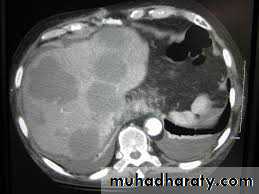

Computed tomography (CT) examination

This technique is complementary to ultrasound, which should usually be performed first. It provides excellent visualization of the liver, pancreas, spleen, lymph nodes and lesions in the porta hepatis. CT allows assessment of the size, shape and density of the liver and can characterize focal lesions in terms of their vascularity.Magnetic resonance imaging (MRI)